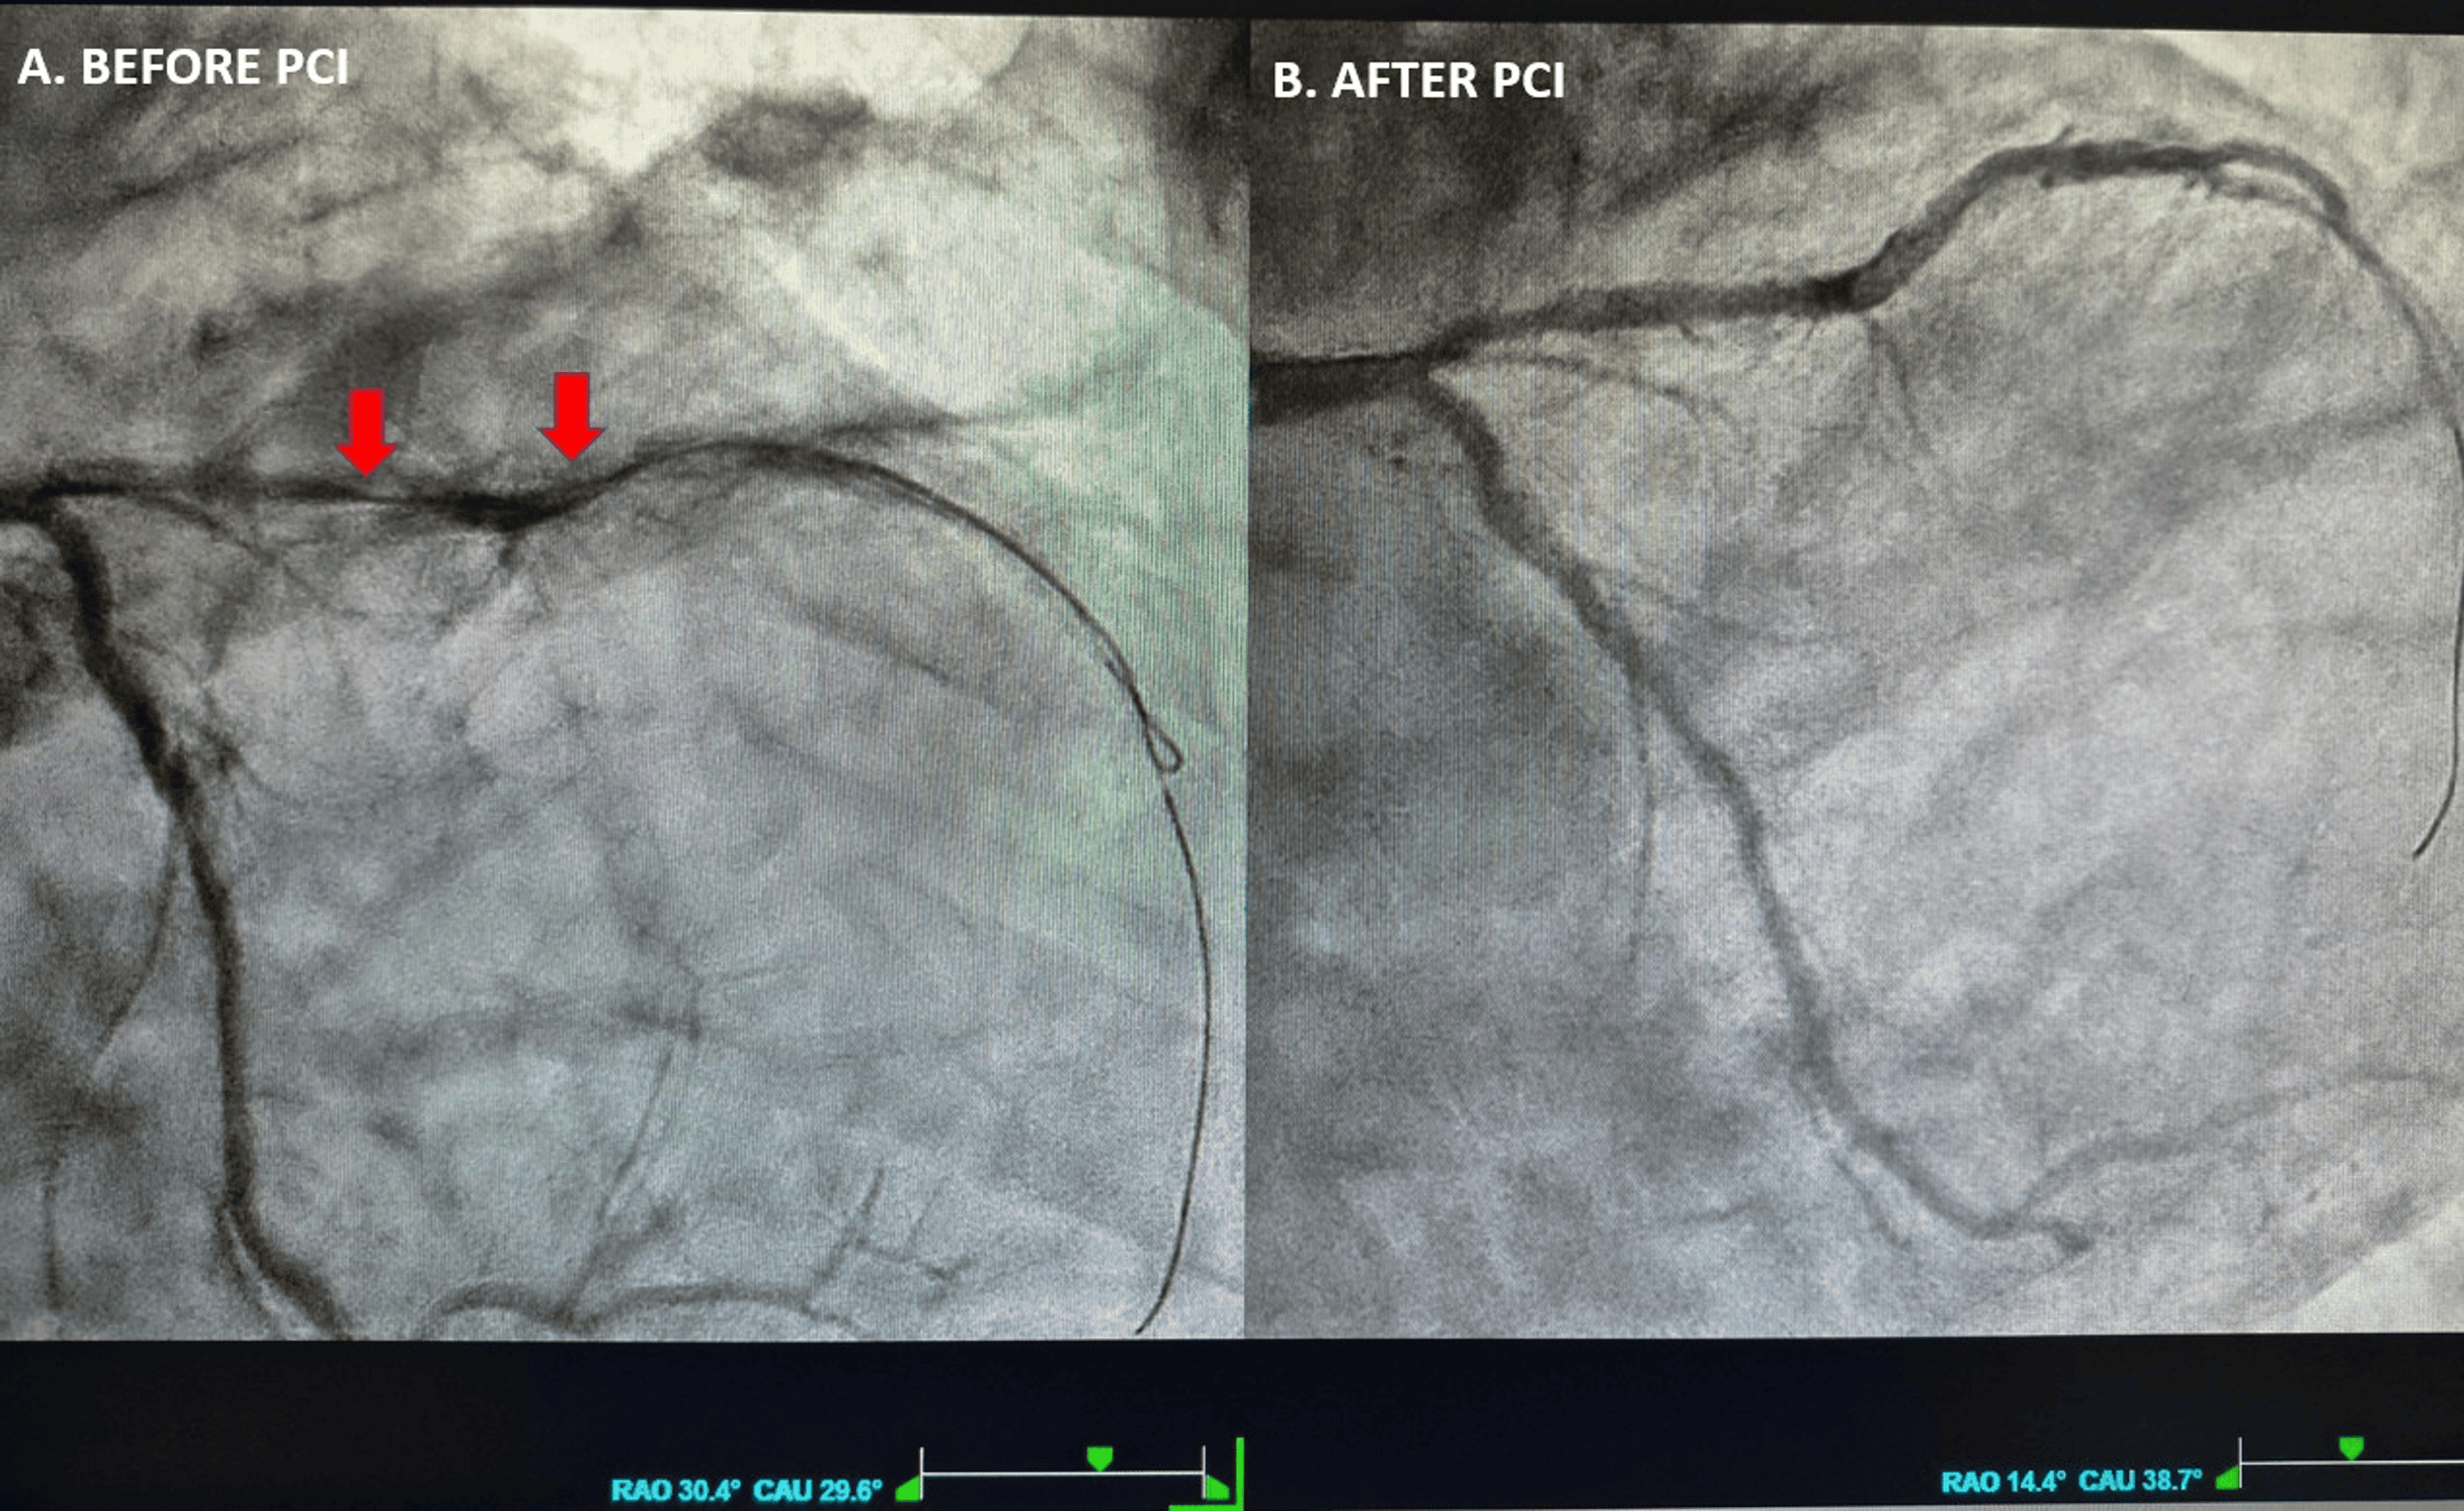

This single-patient case report describes an elderly man presenting with chest pain, hypotension, and bifascicular block (BFB)—a combination of right bundle branch block (RBBB) and left anterior fascicular block (LAFB)—whose ECG showed QRS‑concordant anterior and lateral ST‑segment elevation consistent with a STEMI‑equivalent / occlusive myocardial infarction (OMI) pattern. Urgent coronary angiography revealed a long, severely calcified, near‑occlusive proximal left anterior descending (LAD) artery lesion, successfully treated with primary PCI and drug‑eluting stent implantation, achieving TIMI 3 flow. The Queen of Hearts (PMcardio) AI‑based smartphone app correctly classified the ECG as STEMI‑equivalent, identified atrial flutter and BFB, and predicted reduced left ventricular ejection fraction, later confirmed by echocardiography (EF 38%). This case highlights BFB with concordant anterior ST elevation as a high-risk marker of proximal LAD culprit OMI and provides anecdotal evidence that specialized AI-enabled ECG interpretation can support rapid and accurate decision-making in ACS.

The initial ECG (page 2) showed atrial flutter with 4:1 AV conduction, complete RBBB, LAFB, and QRS‑concordant ST‑segment elevation in V1–V4 with additional lateral ST elevation (I, aVL, V6) and reciprocal inferior changes, leading to a working diagnosis of anterolateral STEMI in the context of new or presumably new BFB. A second ECG (page 3) demonstrated further progression of anterior ST elevation. The Queen of Hearts app labeled the tracing as STEMI‑equivalent, detected the bifascicular block and atrial flutter, and predicted an EF <40%. Coronary angiography (page 4 and Video 1) revealed a severely calcified, near‑occlusive proximal LAD stenosis, treated successfully with drug‑eluting stent implantation and restoration of TIMI 3 flow; other coronary vessels showed only mild, non‑obstructive disease. Post‑PCI ECG (page 5) showed persistence of BFB but resolution of ST elevation with QRS‑discordant T‑wave changes typical for RBBB. Laboratory testing demonstrated markedly elevated high‑sensitivity troponin I and NT‑proBNP with moderate anemia and chronic kidney disease (Table 1, page 6). Echocardiography (Video 2) confirmed apical akinesia, anterior/anteroseptal hypokinesia, EF 38%, biatrial enlargement, and moderate ischemic mitral regurgitation, consistent with the AI‑predicted LV dysfunction. The in-hospital course was uncomplicated, and the patient was discharged after eight days on optimized heart failure and antithrombotic therapy.